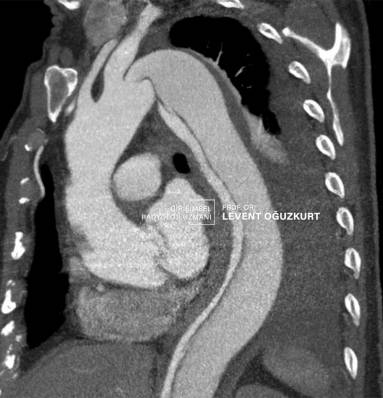

Aort diseksiyonlarının tanısı öncelikle klinik şüphe ile olur. Hasta genellikle şiddetli ağrı nedeniyle acil kliniğe başvurur. Acile şiddetli yırtılır derecede sırt ağrısı ile gelen bir kişide öncelikle aort içi zarında ayrılma düşünülür. Tanı için radyolojik görüntüleme yöntemlerine ihtiyaç vardır. Genellikle bilgisayarlı tomografi ya da kardiyoloji uzamnın yapacağı eko (ekokardiyografi) ile kesin tanı konabilir. Damar yırtılmasına eşlik eden damar anevrizması yani balonlaşması varsa o da kesin olarak belirlenir.